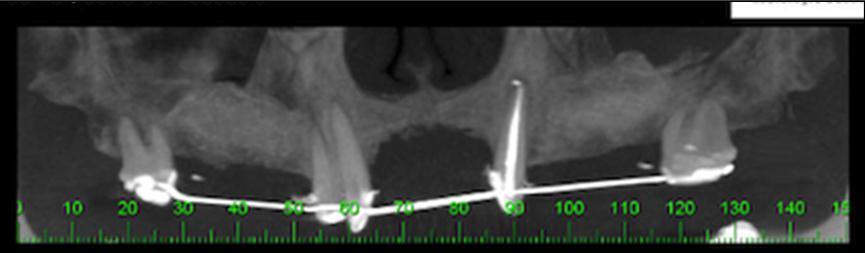

A 49-year-old female presenting a severely resorbed pre-maxillary as a result of previous autogenous bone graft presented to the clinic. Treatment plan was conducted by means of the fabrication of a prototype anatomic model by means of a CBCT scan (Figure 1). A titanium mesh was fabricated on this model to shape an ideal ridge, with normal height and width. Four dental implants were planned to substitute teeth number 7, 8, 9 & 10 for single unit crowns.

Figure 1.CBCT showing presence a significant bone defect of the pre-maxilla.